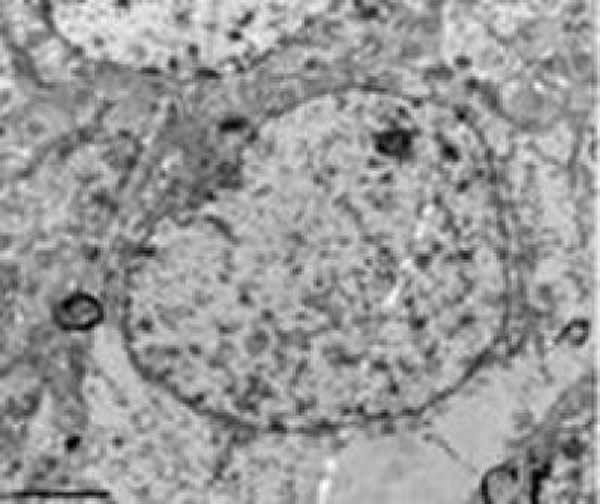

注射dl-3n丁基苯酞后,弥漫性脑损伤大鼠的大脑皮质神经细胞损伤明显减轻,核仁清晰,核膜平滑、连续性较好,线粒体形态基本规则,大多数嵴完整,排列紧密规律,基质颗粒极少量脱落

实验建立大鼠弥漫性脑损伤模型,然后立即腹腔注射dl-3n丁基苯酞(低剂量80mg/kg,高剂量160mg/kg)。结果发现dl-3n丁基苯酞可以减轻脑超微结构的损伤程度,减轻血脑屏障通透性和脑水肿,同时增加血管密度和脑血流量,以及改善运动和感觉功能。说明,dl-3n丁基苯酞可能通过改善微循环障碍,减轻血脑屏障损伤和脑水肿,对弥漫性脑损伤产生保护作用。